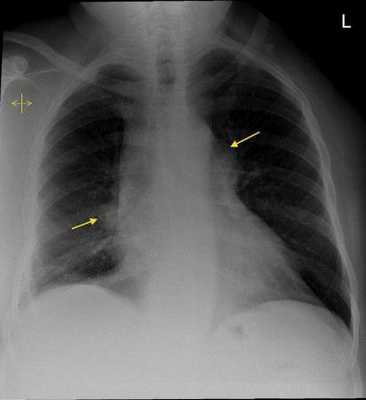

- двусторонняя симметричная внутригрудная лимфаденопатия на рентгенограммах грудной клетки, выполненных в прямой проекции, имеющая характерный вид "крыльев бабочки";

На рентгенологическом снимке можно заметить характерное увеличенние лимфоузлов, а также фиброзные отложения. Это помогает убедиться в случае поражения легких.

Он характеризуется увеличением лимфатический узел рядом с внутренним граница легких (называется "веселый лимфаденопатия ") как видно на рентгеновский снимок, и нежные красные узелки (узловатая эритема ) обычно присутствуют на голенях, преимущественно у женщин. Он также может сопровождаться артрит (более заметен у мужчин) и высокая температура. Артрит часто бывает острым и поражает нижние конечности. [2]

Синдром Лёфгрена состоит из триады: узловатая эритема, двусторонняя внутригрудная лимфаденопатия на рентгенограмма грудной клетки, и боль в суставах. [ нужна цитата ]

Триада узловатой эритемы, острого артрита и двусторонней внутригрудной лимфаденопатии очень специфична (> 95%) для диагностики синдрома Лёфгрена. Когда присутствует триада, дальнейшее тестирование с дополнительной визуализацией и лабораторными исследованиями не требуется. [ нужна цитата ]